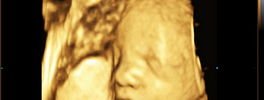

4D Foetal Face

4D Sonography -Foetal Face